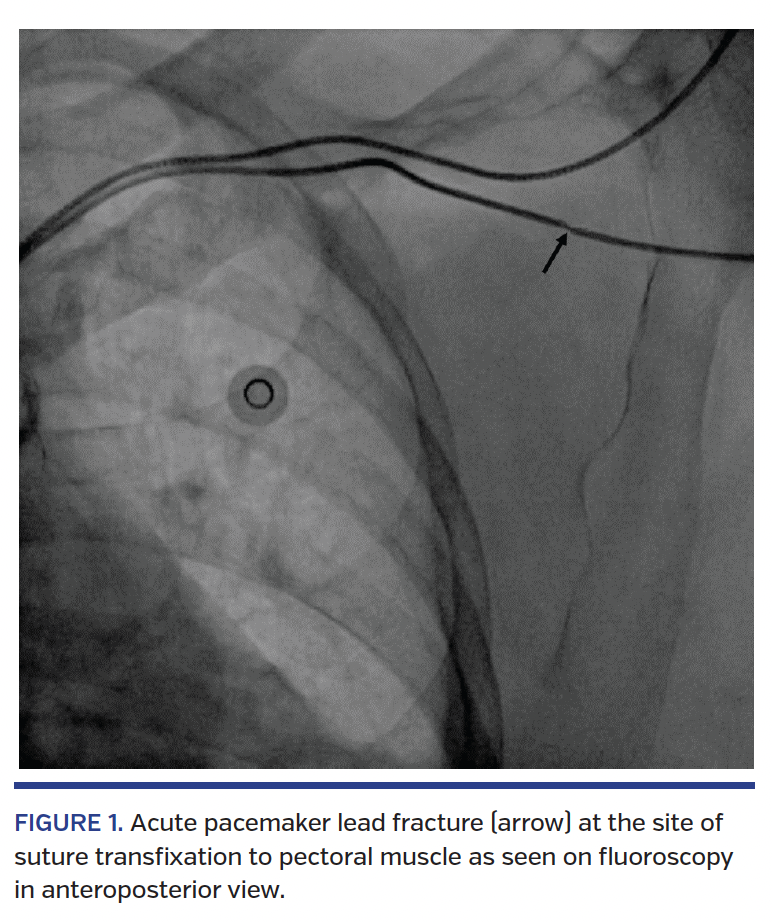

A 75-year-old woman underwent dual-chamber permanent pacemaker implantation in view of recurrent presyncope and excessive fatigue secondary to complete heart block. An active ventricular lead was placed at the right ventricular apex and screwed in after good pacing parameters were achieved. The lead was transfixed by suturing the sleeve to the pectoral muscle. To our surprise, there was a significant rise in lead threshold. A lead dislodgment while suturing the sleeve was suspected. However, on fluoroscopic examination the lead was adequately positioned, but a lead fracture was apparent at the suturing site (Figures 1 and 2). The lead was replaced with a new lead and the procedure was successfully completed without any complications.

Fractures of pacemaker leads are well reported, with the most common site near the subclavian vein entry site due to entrapment between the clavicle and first rib. Direct trauma and excessive movement of the upper limb are common causes. To the best of our knowledge, acute lead fracture during pacemaker implantation has not been reported. Suturing the lead without the sleeve might damage the lead. However, in the present case, this important precaution was carefully taken. Significant lead damage was immediately detected in this case, which led to rectification of the problem. Minor trauma to the lead at this important step may affect the lead outcome in the long term. Tying knots tightly but not too vigorously is suggested, as this carries potential to damage the lead.